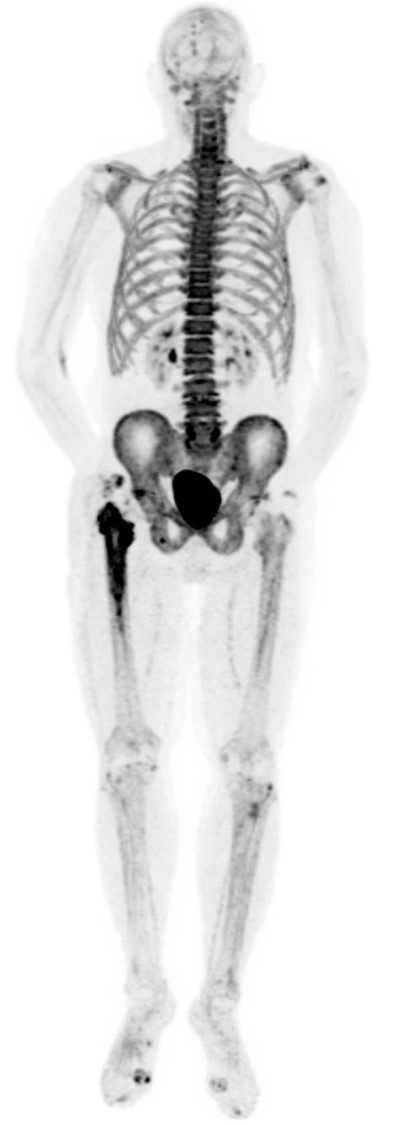

Normal whole body pediatric and adult bone scintigraphy with technetium 99m methylene diphosphonate (MDP) display different features (figure 1). In the pediatric population there is intense radiotracer uptake in the growing physes of long bones. Normal adult whole body planar bone scans with Tc-99m MDP demonstrates normal expected uptake in the bilateral sacroiliac joints, iliac crest, acromioclavicular joints, sternoclavicular joints, and nasal region. Normal radiotracer activity is excreted into the kidneys and urinary bladder.

Normal adult whole body bone scan Tc-99m MDP demonstrates normal expected uptake in the bilateral sacroiliac joints, iliac crest, acromioclavicular joints, sternoclavicular joints and nasal region. Normal radiotracer activity is excreted into the kidneys and urinary bladder. |